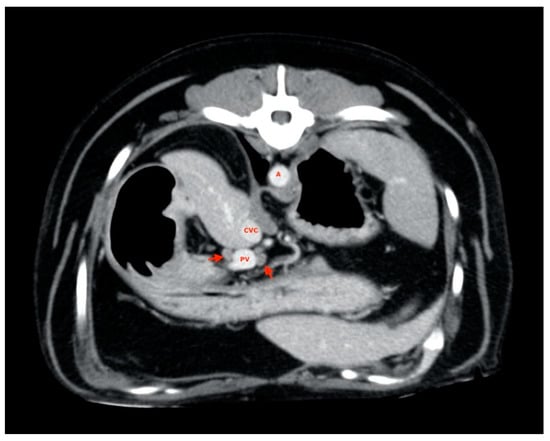

2.4. Procedures

2.5. Measurements